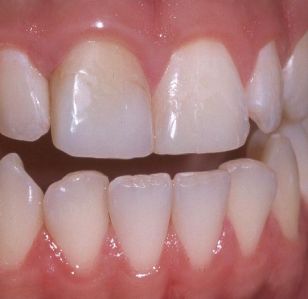

Este paciente tenía una corona de metal cerámica antiestética con un poste de metal de gran tamaño con el efecto grisáceo en el margen cervical. Aunque el color de la corona es aceptable para el paciente, la color a nivel gingival era inaceptable y exagerado, especialmente debido a la amplia sonrisa de la paciente. Ella quería reemplazar la corona por un central más estético.

Se retiró la corona. Todo el diente estaba decolorado. Se eliminó todo residuo de eugenol limpiando el canal radicular con alcohol al 75%. Se realizó un blanqueamiento del incisivo central. Antes de este blanqueamiento se selló el canal radicular con un cemento de ionómero de vidrio para evitar la filtración del material de blanqueamiento en el conducto radicular. Después de esto, el diente quedo listo para ser restaurado estéticamente.